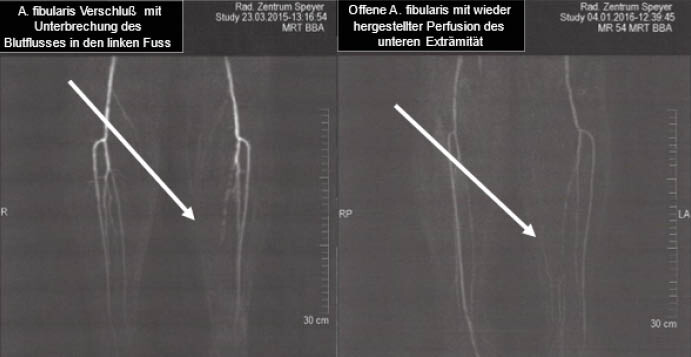

Eine 56-jährige Patientin (Akademikerin) litt seit über 40 Jahren an Typ-1-Diabetes mellitus. Sie wurde seit ihrer Manifestation intensiv mit Insulin behandelt, aber aus panischer Angst vor Hypoglykämien lagen ihre Blutzuckerwerte schon immer mehrheitlich in einem hyperglykämischen Bereich (HbA1c: 10,9 %). Sie hatte seit mehr als fünf Jahren eine bekannte periphere Neuropathie, und seit mehr als zwei Jahren bestand ein nicht heilendes chronisches Geschwür unterhalb der linken Ferse (Abbildung 1A). Drei Monate vor unserer Intervention wurde in einem Angiogramm ein vollständiger Verschluss der Arteria fibularis festgestellt (Abbildung 2A). Am linken Bein waren keine Fußpulse tastbar, und mit der Laser-Doppler-Fluxmetrie konnte dort auch kein Blutfluss nachgewiesen werden. Aufgrund dieser Befunde wurde die Amputation des linken Unterschenkels als einzige verbleibende Option zur Verbesserung der Prognose der Patientin in Betracht gezogen. Als letzter Ausweg und unterstützt durch frühere (prä)klinische Ergebnisse [Ozegowski 2008, Burgard 2015] wurde versucht, den katastrophalen Zustand durch die intravenöse Anwendung von Hyaluronidase zu verbessern (experimenteller Heilversuch, Off-Label).

Es wird davon ausgegangen, dass die Hyaluronidase-Infusionen eine breitere Remodulation der Glykokalix bewirken, die über einen Zeitraum von mehreren Wochen und Monaten anhält und die Patientin wurde daher in der Folgezeit mehrmals wieder einbestellt. Das Ulkus heilte innerhalb der nächsten drei Monate vollständig ab (Abbildung 1B). Im Angiogramm nach 6 Monaten, das von demselben Radiologen durchgeführt wurde, der auch die vorherige Untersuchung vorgenommen hatte, wurde eine Wiedereröffnung der Arteria fibularis festgestellt (Abbildung 2B). Die Fußpulse waren tastbar, und mittels Laser-Doppler-Fluxmetrie wurde ein erheblicher Blutfluss gemessen. Die geplante Amputation wurde abgesagt, und die Patientin konnte ihr normales Leben mit besserer Blutzuckereinstellung (HbA1c nach 6 Monaten 7,5 %) und guter Hoffnung für einen langfristigen Erhalt des Beins fortsetzen (bisheriger Beobachtungszeitraum: 7 Jahre).